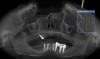

Figure 24  Postoperative CT scan demonstrated horizontal bone regeneration.

Figure 24

Figure 25  Postoperative CT scan demonstrated horizontal bone regeneration.

Figure 25

At approximately 3 weeks after implant surgery, four of the eight free-gingival “plugs” appeared incorporated over the underlying implants, and no communication with the cover screws was evident (Figure 23). A postoperative CT scan demonstrated horizontal bone regeneration compared to the preoperative situations, as demonstrated in the region of tooth No. 9 (Figure 24 and Figure 25).